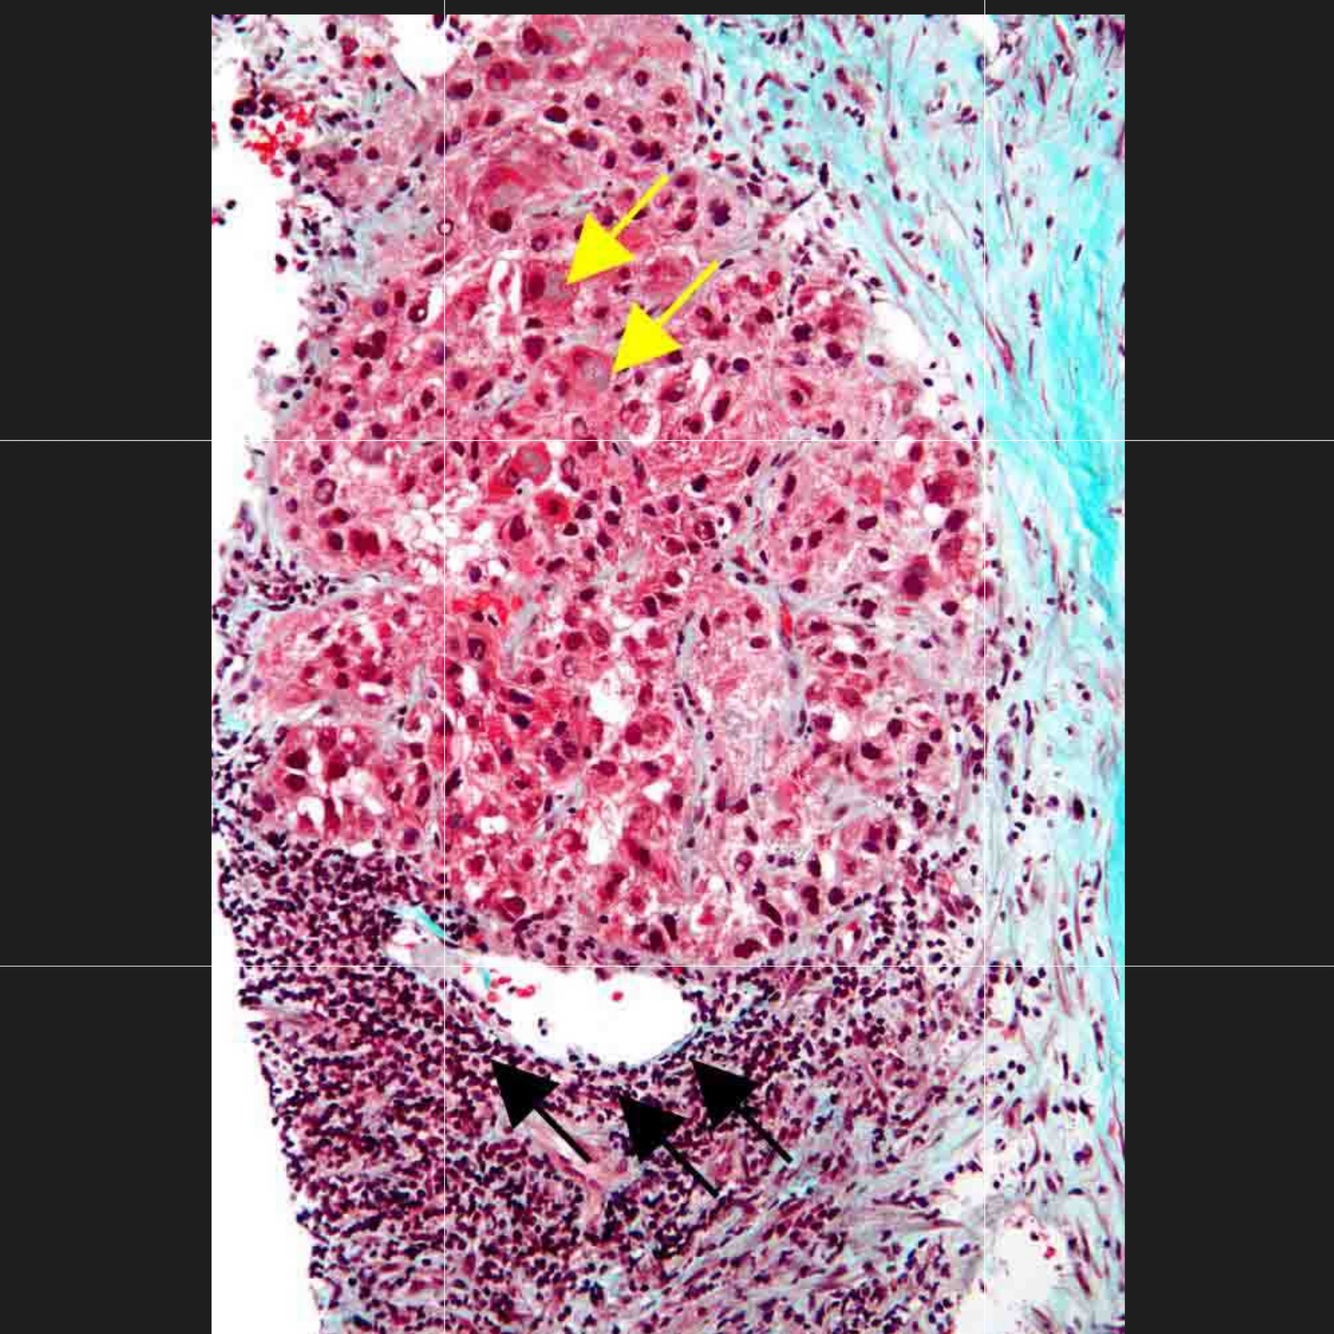

alcohol-associated hepatitis: Fatty changes (macro- and microvesicular), Mallory bodies, and a neutrophilic infiltrate

Mallory body

Councilman bodies,